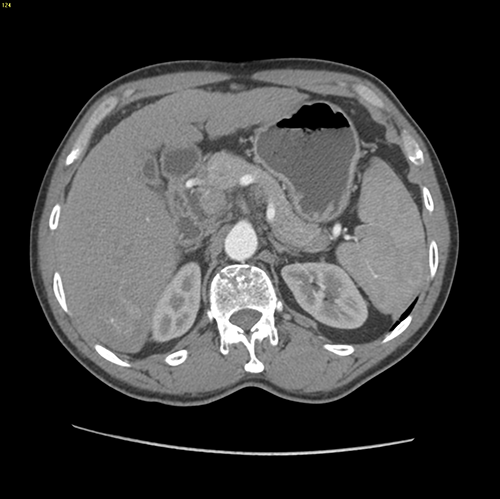

S67肝癌--腹腔镜S67切除